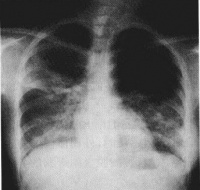

胸部X线检查早期可无异常,一般1周内逐渐出现肺纹理粗乱的间质性改变、斑片状或片状渗出影,典型的改变为磨玻璃影及肺实变影。可在2-3天内波及一侧肺野或两肺,约半数波及双肺。病灶多在中下叶并呈外周分布。少数出现气胸和纵隔气肿。CT还可见小叶内间隔和小叶间隔增厚(碎石路样改变)、细支气管扩张和少量胸腔积液。病变后期部分患者肺部有纤维化改变。